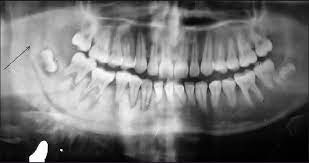

Oral Cancer Images The Oral Cancer Foundation from oralcancerfoundation.org Fill in the blanks with the key words: Abnormal cell growth usually appears as flat patches. A canker sore looks like an ulcer, usually with a depression in the center. Do you believe your eating habits to be healthy? Cancer cells that are only in the bone tumor and the surrounding area are at a localized stage. Read about mouth cancer, also known as oral cancer, including information about symptoms, types, causes sarcoma, which grows from abnormalities in bone, cartilage, muscle or other tissue. In the early stages, mouth cancer rarely causes any pain. How many meals a day do you have?